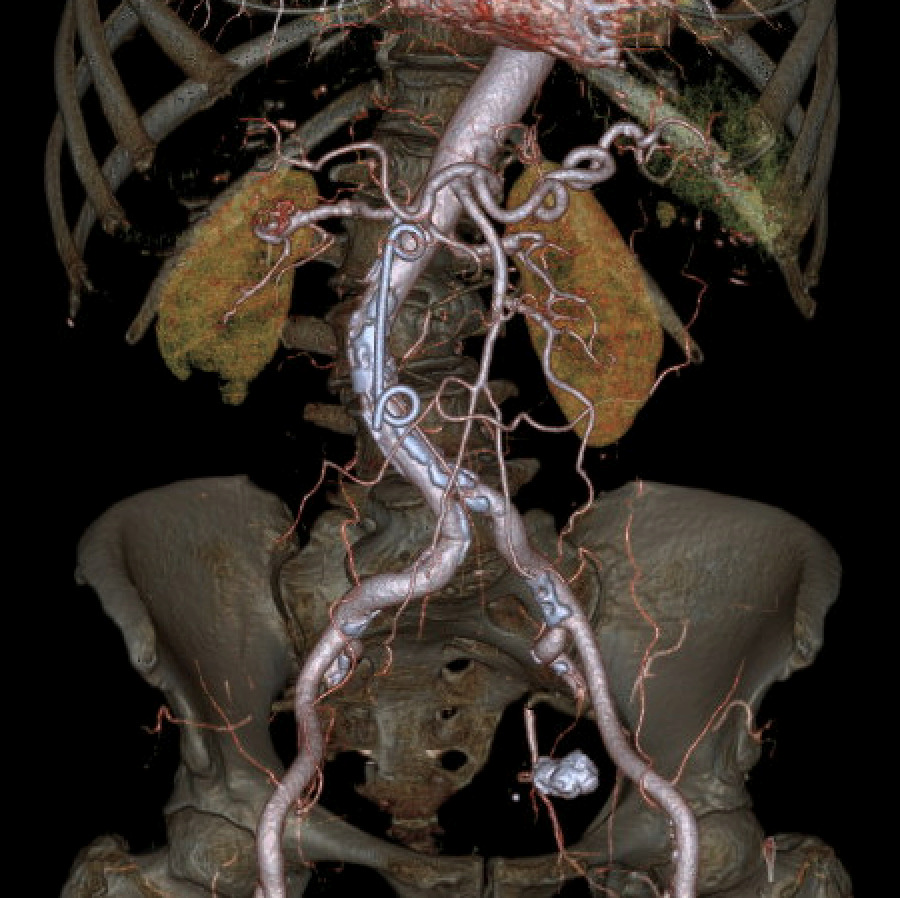

Further evaluation with Doppler ultrasound demonstrated non-occlusive bland thrombus within the common hepatic and left hepatic arteries. A subsequent CT angiogram (CTA), performed four weeks after the initial CT, confirmed the presence of multiple visceral pseudoaneurysms involving the hepatic arterial system. These included aneurysms of the right hepatic artery measuring 5.5 mm and 5.8 mm, intermediate hepatic artery aneurysms measuring 7.7 mm, 5.7 mm, and 14 mm, and a left hepatic artery aneurysm measuring 10.4 mm. Additionally, the coeliac trunk appeared diffusely aneurysmal with associated luminal irregularity (figure 3). All aneurysms demonstrated interval enlargement compared with prior imaging (Figure 2). Notably, during this period, the patient’s inflammatory markers and liver function tests had normalised.